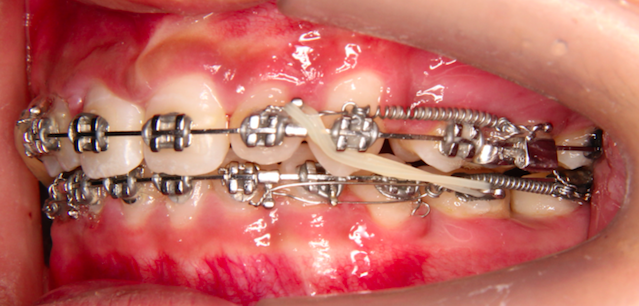

1、口腔正畸目前开展的项目有:错颌畸形的系统规范的检查、诊断测量分析,各类错颌畸形的正畸治疗,直丝弓固定自锁托槽矫正、种植支抗钉技术、隐形矫正(隐适美、时代天使);

杨春波,大学本科,住院医师,中共党员,2014年在昆明医科大学附属口腔医院正畸科进修学习一年;2018年在昆明医科大学附属第一医院口腔颌面外科进修学习半年,2022年10月至2023年3月在上海市第一人民医院口腔科进修学习口腔种植、青少年专病错颌畸形;主要擅长青少年及成人牙列拥挤、深覆牙合、深覆盖、地包天、下颌后缩等各类牙颌面畸形的正畸治疗,隐形矫正,口腔种植牙修复、各类复杂牙列缺损活动义齿修复、数字化吸附义齿修复、固定义齿美容修复。